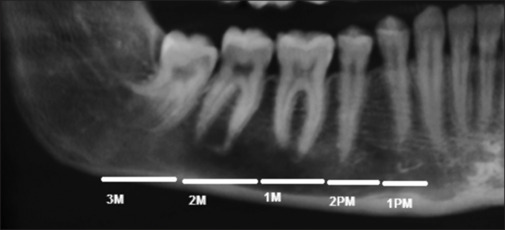

Materials and methods: In this retrospective study, 132 mandibular cone-beam computed tomography images of patients with MCI1 were evaluated. 6-point rating MCV score and CR were determined for cross-sections of the MC in the following areas: incisive canal (INC), mental foramen and canal (MF), first premolar to the third molar (1PM, 2PM, 1M, 2M, and 3M), and the corresponding edentulous areas (E1PM-E3M). 1PM was overlapped with MF in most cases. An MCV score1 (excellent visibility) and 2PM area were considered reference levels.

Results: Sex and age did not significantly affect the MCV score or CR (P > 0.05). 98.6% of the INC and 92.31%-100% of the MC were visible. The mean ± SD of the CR in the INC and MC was 0.86 (0.23) and 0.77 (0.29), respectively. The estimated difference in the mean CR was statistically significant only between the INC area and dentulous areas (P < 0.001).